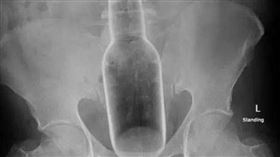

男將花露水瓶塞肛門!曝原因醫師傻眼

異物卡在體內的案例時有所聞,醫師們面對這些五花八門的...